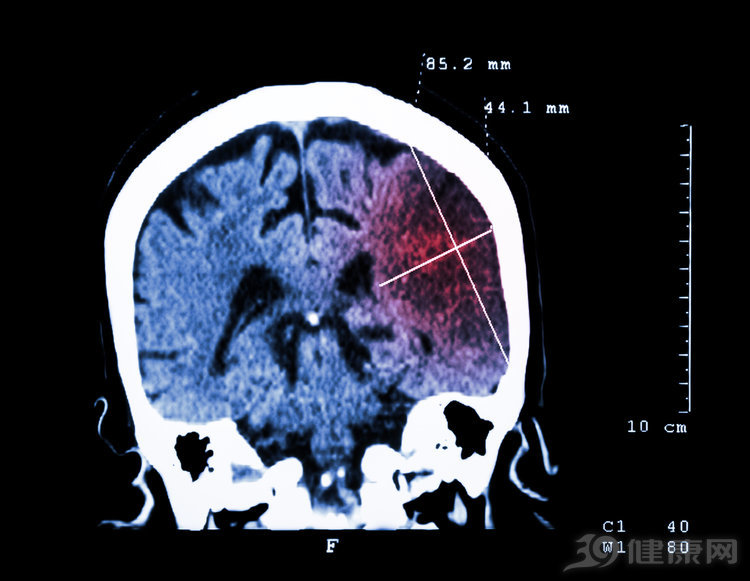

脑梗 , 是由于脑血管出现堵塞 , 引起脑部组织供血不足 , 进而造成的脑组织缺血性坏死 。

更令人担忧的是 , 脑梗发病隐匿且紧急 , 往往突然发生 , 且抢救的黄金时间只有2小时左右 , 及时发现并治疗或许可以把身体受到的伤害降至最低 。